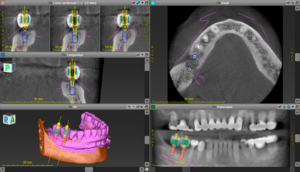

インプラントの診断に際し、CT(立体的なレントゲン画像、1枚目の画像)とステント(インプラントを埋める方向を再現する装置、2枚目の画像)を使っているかで判断していただくのがよいかと思います。

組み合わせることによって3枚目の画像のような設計ができるようになります。

危なくないインプラント治療を行うことができます。